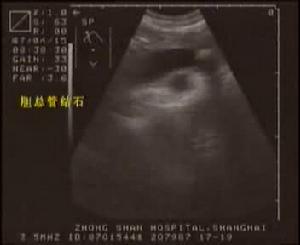

膽總管結石B超診斷檢查

3.B型超音波檢查雖然價廉無創,對膽囊結石的準確率達98%,但因受十二指腸等空腔臟器的影響,對膽總管結石的準確率僅為50%左右,特別對十二指腸後段膽管難以顯示。假陽性及假陰性率均較高。